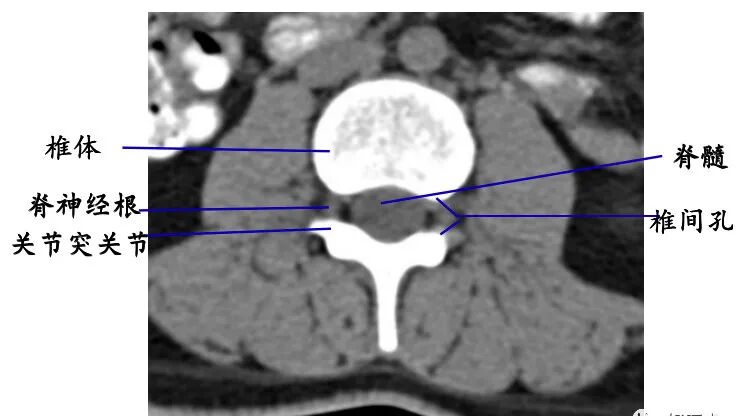

2. 经椎体下部的横断层面:

断面经过的部位:椎弓根下方的椎体。

主要特征:椎管为不完整的骨性环,其断开处为椎间孔上部。

经过不同部位的椎间孔上部的结构不同,颈段主要为椎间静脉,胸、腰段主要为脊神经根。

4. 椎管及内容物

硬膜外脂肪:低密度影

硬脊膜囊:呈圆形或椭圆形软组织密度影。CT平扫不能区别硬脊膜囊、脑脊液和脊髓。

椎内静脉丛:位于硬膜外间隙内,在CT平扫上不能单独显示,增强扫描呈点状高密度影。

脊神经根:中等信号条状或圆点状影。

椎间孔:位于椎管前外侧,其内的脊神经根呈软组织密度,周围有低密度的脂肪组织环绕

充填椎间孔的脂肪组织呈高信号;

行走于其中的脊神经根呈圆形、长圆形低或等信号影